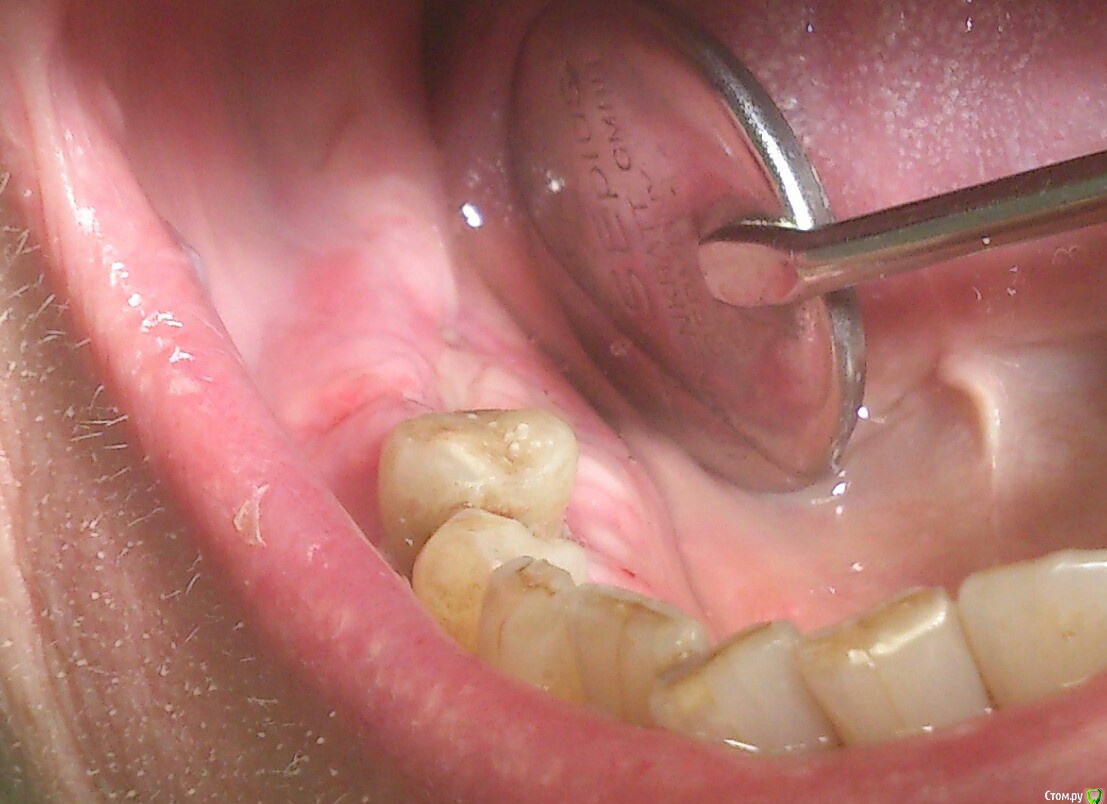

andrey_1965 Опубликовано 21 декабря, 2015 Поделиться Опубликовано 21 декабря, 2015 Ну как результат ?1.-диэпителизация подворот лоскута очень удобно,но опасно для резбы через неделю.язычно-механическая травма через 10 дней через 3недели. На временных доформирую рельеф.2. вроде ничего нештатного через 2недели A-PRF через 5недель убрал все,закрыл мембраной A-PRF две поперек,одна в доль через неделю через 13дней через 21день. Следующий осмотр будет на сроке 5 недель(думаю все сравняется) 3. через неделю 2недели 3недели,на дистальных отмываю помойку4 недели Ссылка на комментарий